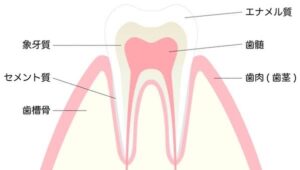

歯の構造

まず、歯の構造について少しお話を・・・

私たちの歯は主に3つの組織から構造されいます。

エナメル質

歯の表面の一番外側部分を‘‘エナメル質’’と呼びます。

エナメル質の厚さは2〜3ミリ程度で、人間の組織の中で一番硬い組織なんです!

半透明で、酸に溶けやすい特徴があります。

象牙質

エナメル質の内側にある組織が”象牙質’’です。

象牙質は歯の大部分を占めていて、黄色みがかった色をしています。

個人差はありますが、象牙質の色がその人の基本的な歯の色調(歯の白さ)となります。

エナメル質より柔らかい組織なので、虫歯が象牙質まで到達すると、進行が早くなります。

歯髄(しずい)

神経線維や血管などが通っている組織のことです。

一般的には“神経’’と呼ばれ痛みを感じる部分になります。

象牙質への栄養補給、炎症など刺激に対する防御の役割もあります。